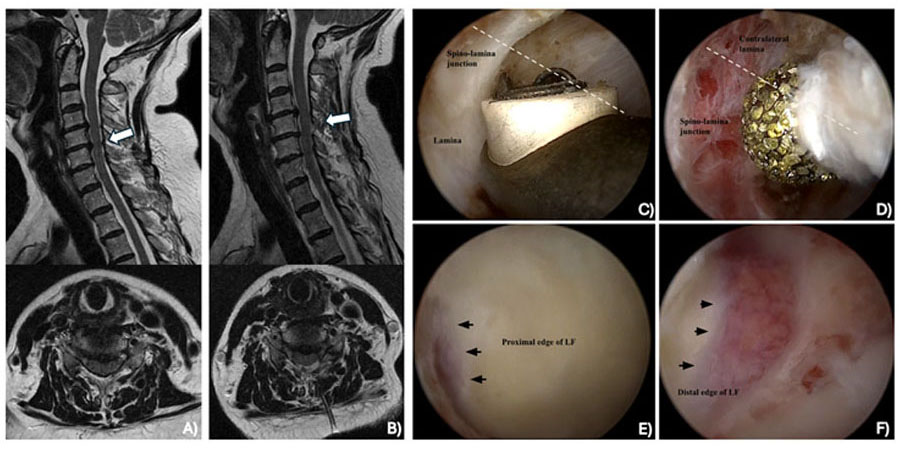

Recent interest has shifted toward motion-preserving surgical techniques, including cervical disc arthroplasty (CDA), endoscopic cervical spine surgery, laminectomy without fusion, and laminoplasty. Yet, evidence and best practices for these techniques in the context of DCM remain underexplored.

By Ryan Wang, Satheeshram Tamilselvan, Ji Soo Ha, Aditya Vedantam, C. Rory Goodwin, Nathan Evaniew, Uzondu F Agochukwu, Konstantinos Margetis, Yoon Ha, Michael Fehlings, Jefferson R Wilson, Ankit Mehta - Cervical Laminectomy for degenerative cervical myelopathy: Is there a role in the modern day? A systematic review and meta-analysis